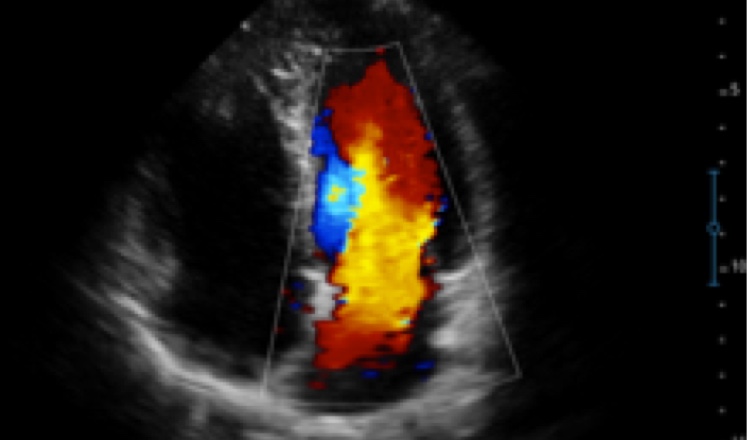

X5采用前端的超声专用芯片,将台式机大规模集成电路完美压缩在笔记本超声的精巧下,提高了系统的运算速度,加载μ-Scan微米成像、脉冲反相谐波等技术,带来优异的临床表现,清晰呈现高分辨率二维图像和层次丰富的血流图像